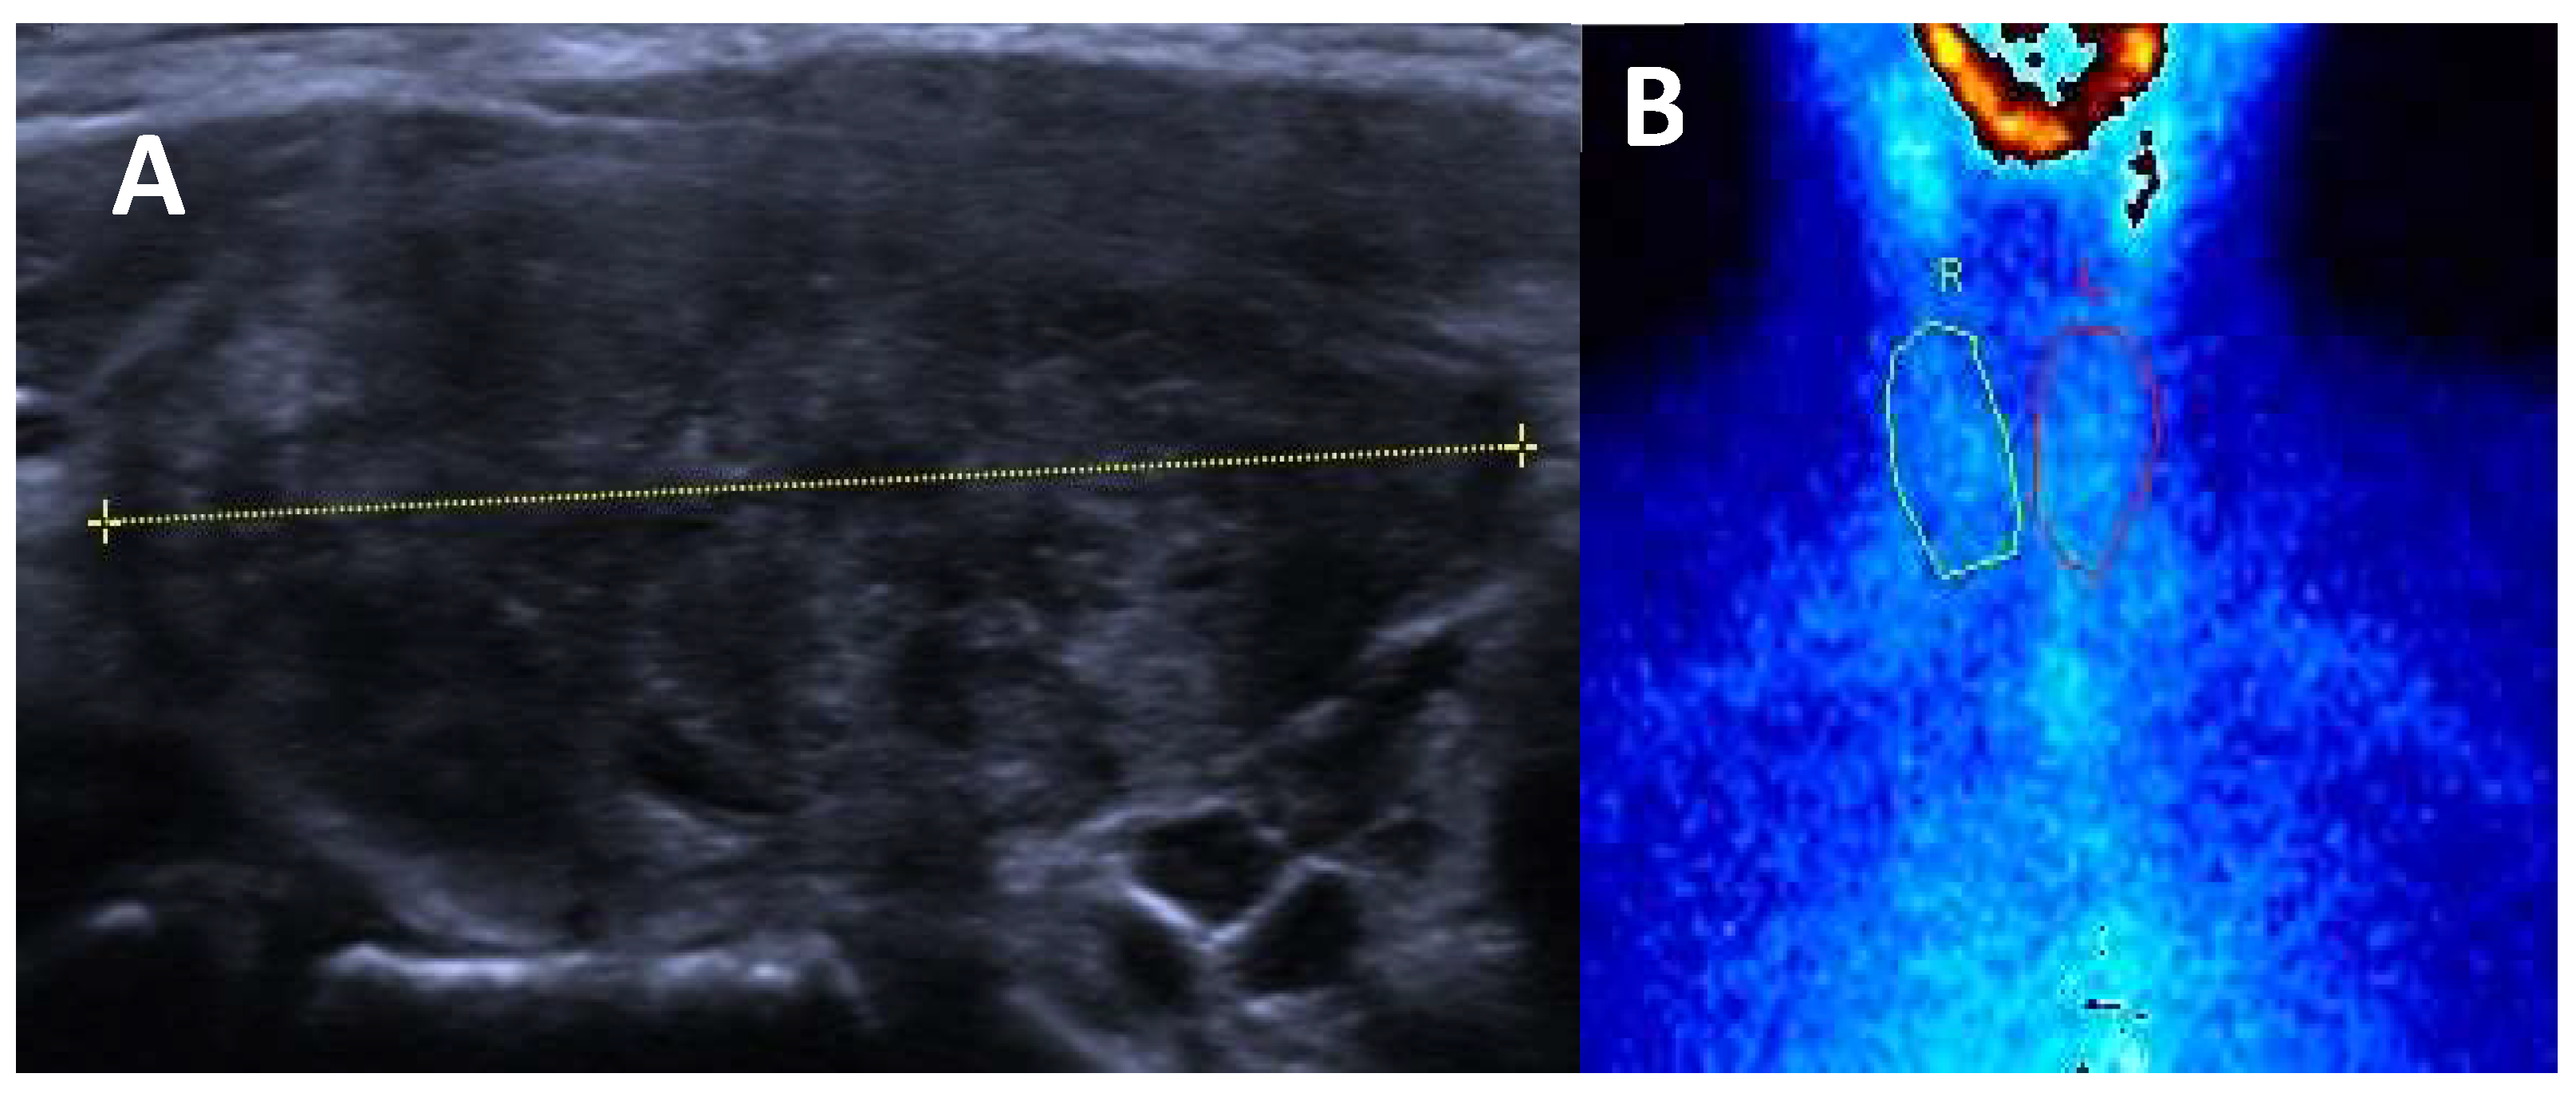

3.2.1. Graves’ Disease

- Diffuse Enlargement: the thyroid is typically symmetrically enlarged.

- Increased Vascularity: Doppler ultrasound often reveals increased blood flow within the thyroid, corresponding to heightened metabolic activity.

- Hypoechoic Parenchyma: the thyroid tissue may appear hypoechoic relative to normal tissue, reflecting inflammatory changes.

- Heterogeneous echogenicity: a mild to marked heterogeneity in echotexture may be seen, indicative of autoimmune processes and inflammatory changes within the thyroid gland.